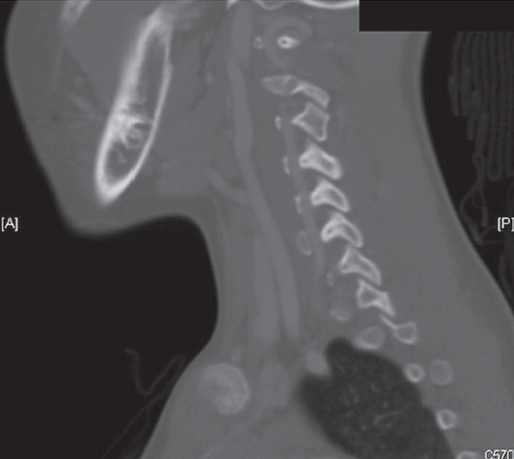

The next day the patient’s CT scan was evaluated by the attending radiologist, who found a right C3-4 facet dislocation. The child was called back to the ED for reevaluation. A neck CT scan with contrast demonstrated a jumped facet at C3, and a kink in the vertebral artery (Figure 1) and normal alignment of the left side (Figure 2).

Figure 2 – This sagittal image shows normal alignment of the left side.